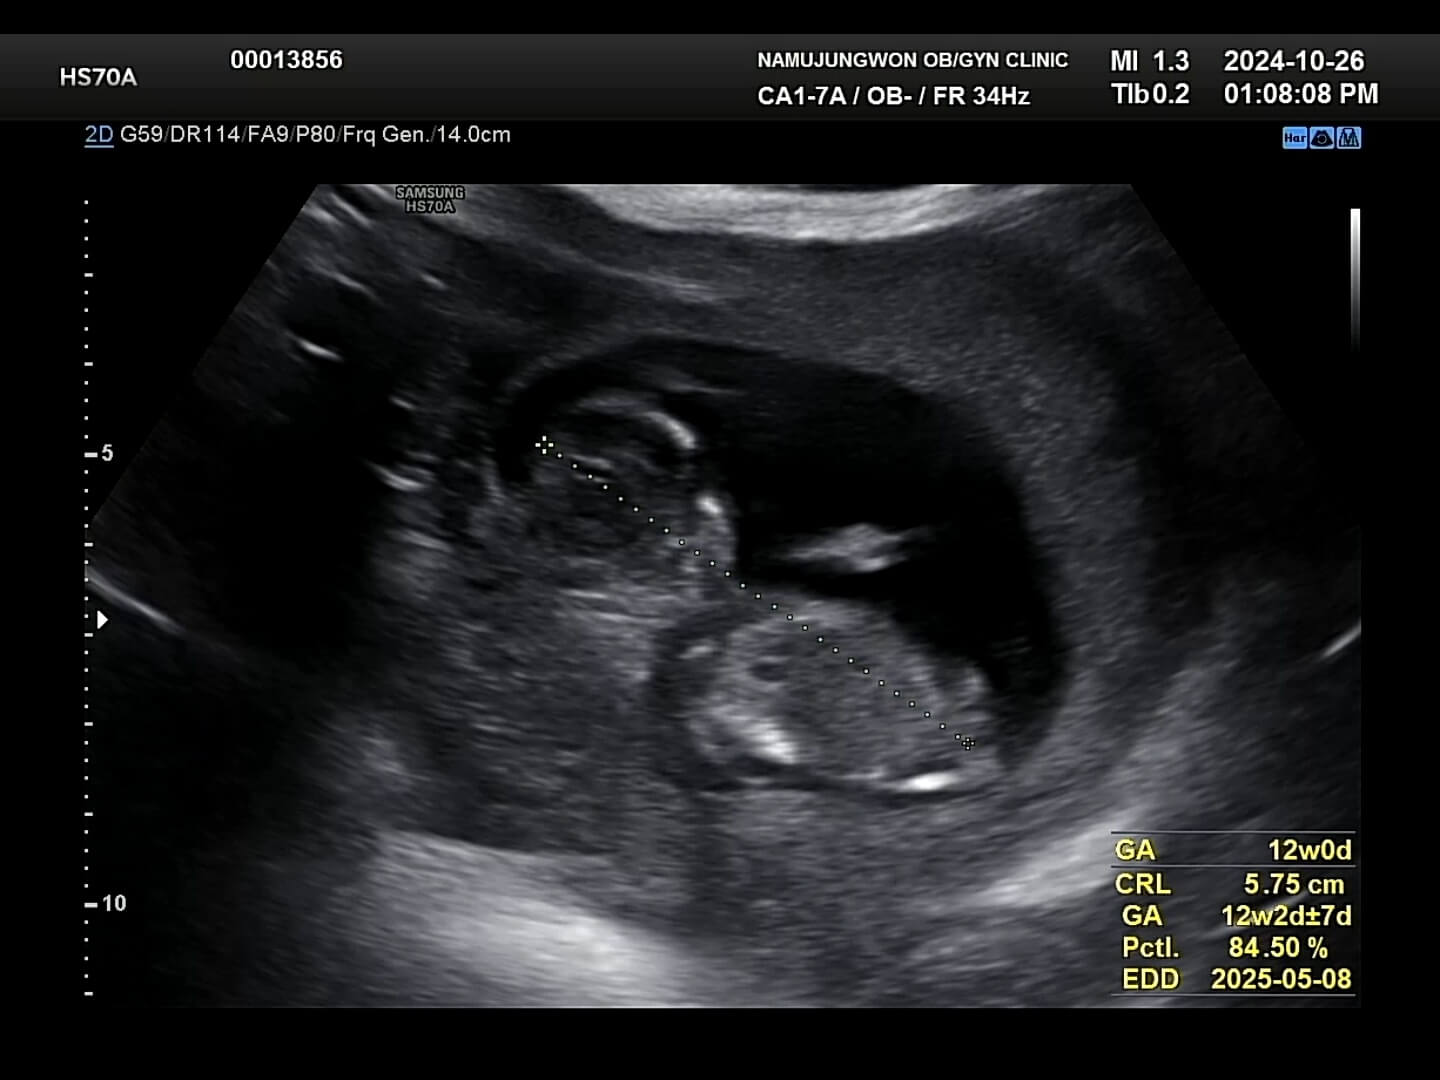

이제 일반 초음파로 목투명대와 코뼈가 잘 형성되었는지 확인합니다. 목투명대는 이물질이 쌓이는 공간이라고 보시면 되고, 이 목투명대가 2.5~3mm 정도 이상되면 기형아 확률이 높아지기에 이때, 융모막 검사나 니프티 검사를 실시하게 됩니다.

목투명대-코뼈 꾸미 목투명대는 다행이 1mm로 통과하였고, 오른쪽 사진을 보시면 얼굴 쪽에 하얀색깔 뼈가 있는데 이게 코뼈라고 하시더라구요. 이 코뼈도 잘 형성되어 있어서 눈으로 확인해주시는 1차적인 검사는 통과했어요. 그리고 나서 피를 뽑았는데요. 12주에 1차 기형아 검사로 피를 뽑고, 16주쯤에 2차 기형아 검사로 피를 또 뽑는데, 이 두 시기에 뽑은 피를 검사해서 최종적으로 기형아 검사 '저위험군'인지 '고위험군'인지 확인이 됩니다. 꾸미는 목투명대와 코뼈가 잘 보여서 일반 기형아검사를 실시하였습니다.

아, 그리고 성별은 원장님께서 80% '블루'라고 보시면 될 것 같아요. 라고 말씀해주셨는데 과연 반전이 일어날까요?